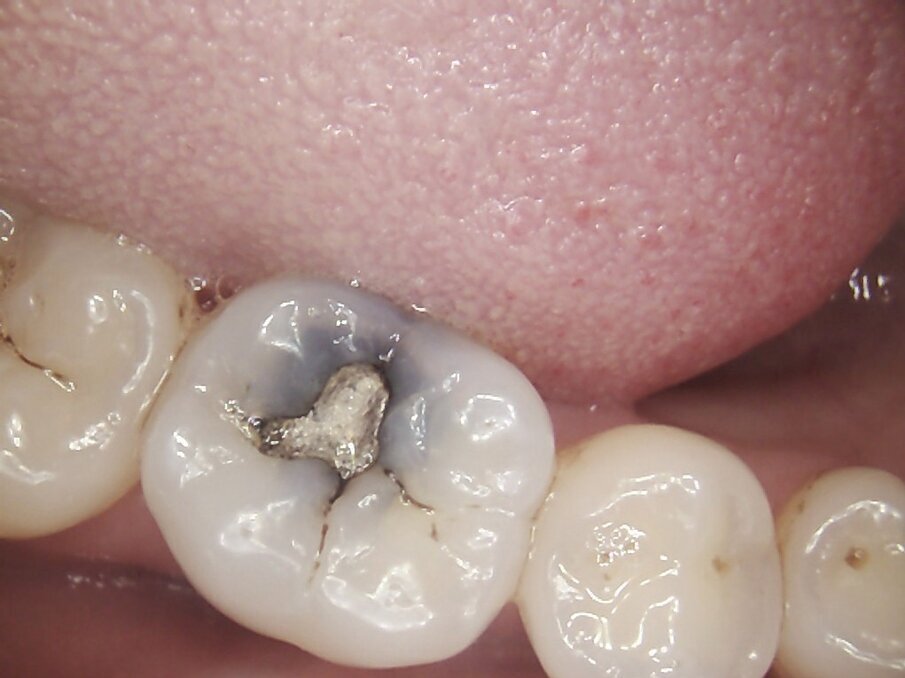

On examination, teeth 16 and 46 had amalgam restorations, with defective margins and signs of corrosion of the metal into the surrounding dentinal tubules. Tooth 46 had a vertical fracture running from occlusal surface to 1mm coronal if the gingiva on the palatal aspect. Neither tooth was tender to percussion and both scored positively with electric pulp testing. However, 46 did have pain on release when biting on the palatal cusps of the crack finder. The patient confirmed this was the sensation she had been experiencing over the last few months. Two periapical radiographs confirmed caries under each amalgam restoration but no evidence of periapical pathology.

I suggested removing each amalgam restoration and any stained dentine and fractures and restoring the teeth with Inlays fabricated by CAD/CAM system, MyCrown.

The amalgam restorations were removed with high volume suction, Swedish clean up suction tips, maximum water flow with High speed hand piece. Appropriate supplements were given to the patients to assist in detoxification and flushing the body of any amalgam particulate which entered the throat and gut. The carious and stained dentine, and fractured weakened enamel was removed with slow speed and maximum water flow.